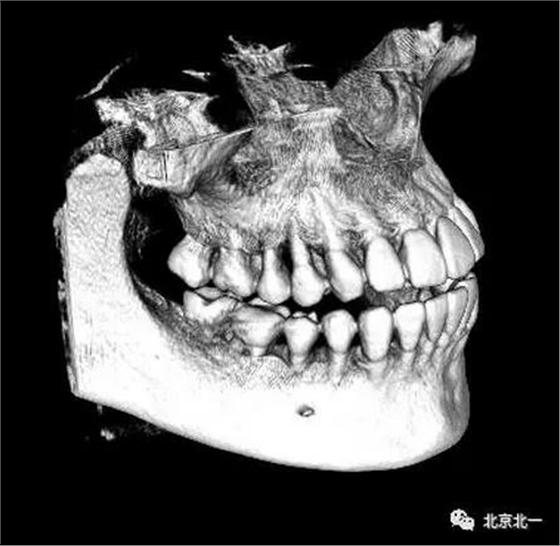

圖二:自帶的CBCT顯示下牙槽神經(jīng)管貼著智齒走形。

圖四:三維重建